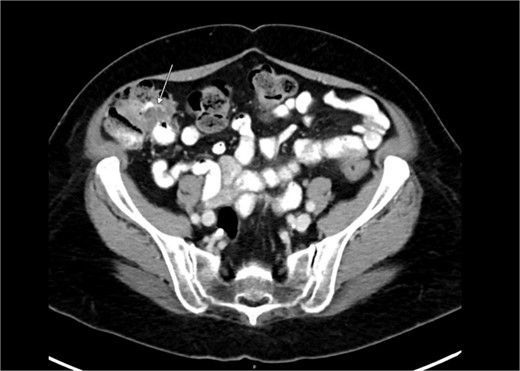

Diagnostic laparoscopy demonstrated multiple cystic lesions throughout the abdomen and pelvis (Figs 3 and 4). The gross appearance of these cysts was consistent with mucinous carcinomatosis. Laparoscopic excisional biopsy of several lesions was performed. Frozen section analysis revealed mucin but did not reveal evidence of metastatic adenocarcinoma. Colectomy was deferred due to concern for carcinomatosis, as if confirmed, she would likely be treated with neoadjuvant chemotherapy, restaging, followed by cytoreductive surgery (to include synchronous right colectomy) with heated intraperitoneal chemotherapy.

Intraoperative view of the pelvis: multiple cysts involving the peritoneum.